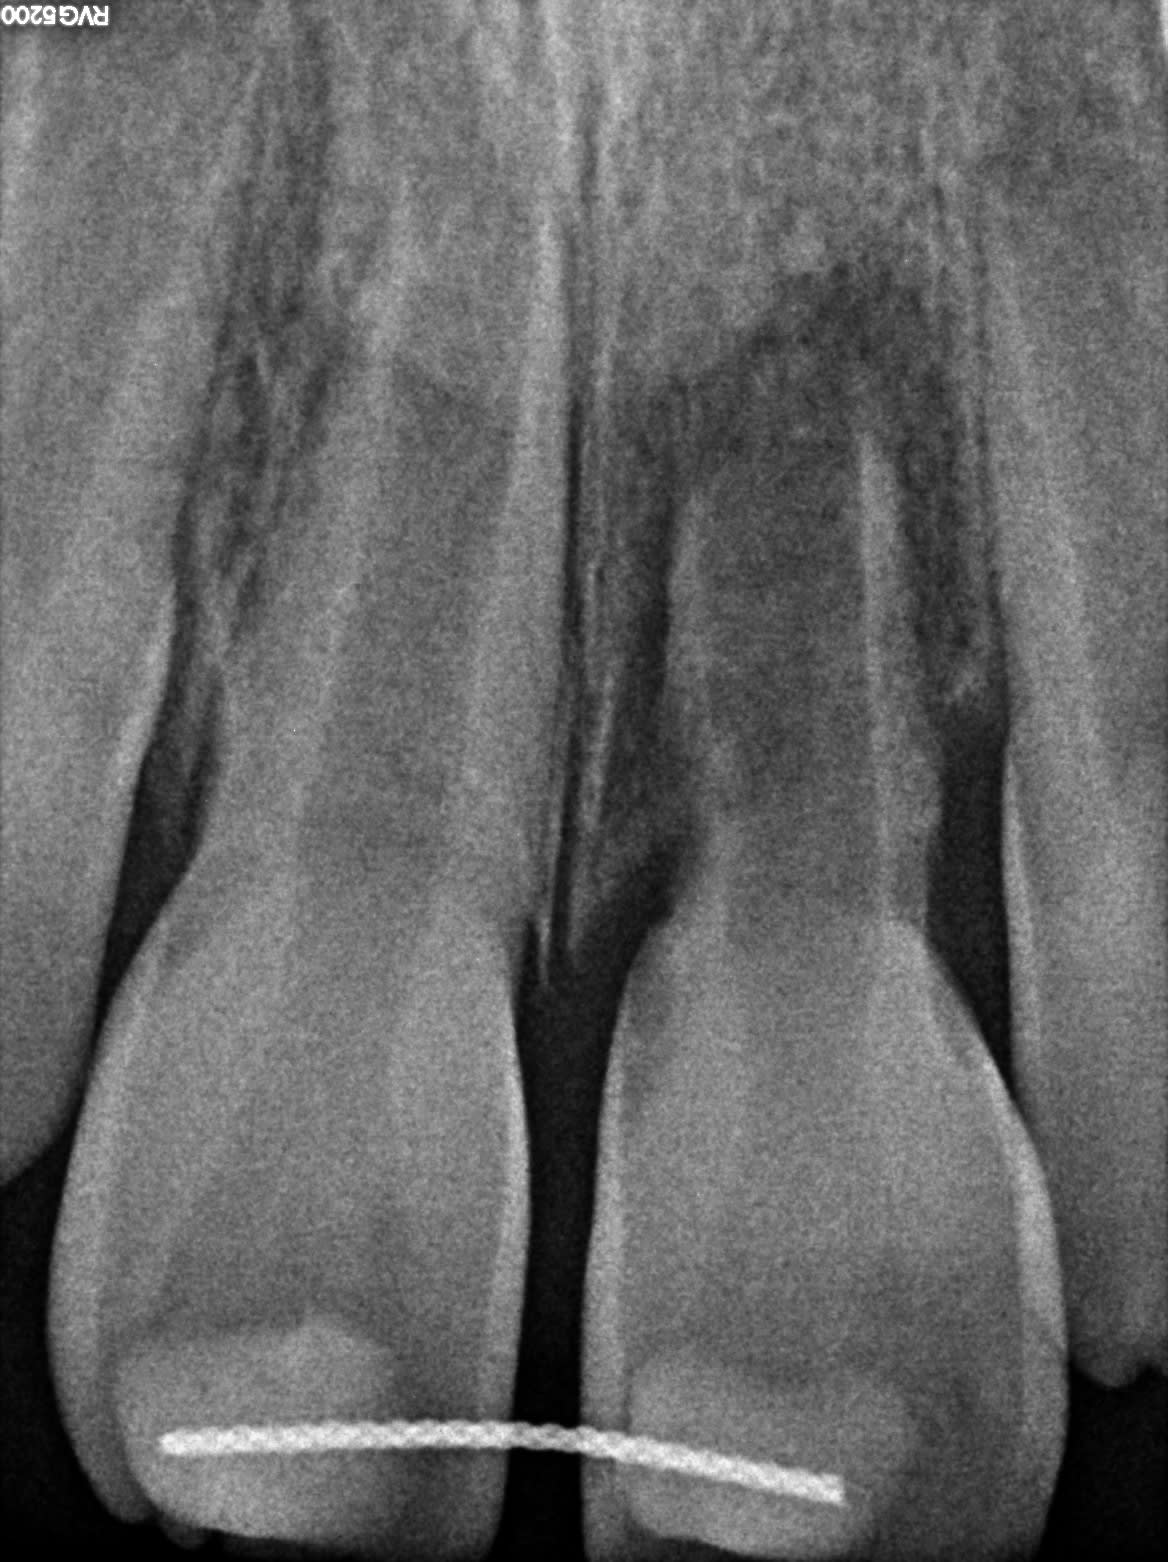

Petite de 6 ans, accident de trampoline début janvier, expulsion de 21 (18h). La maman ne trouvant pas de dentiste emmène sa fille (avec la dent immergée dans de l'eau) aux urgences du chu. Elle est reçue par un médecin généraliste qui la renvoie chez elle avec une ordonnance de doliprane et une invitation à consulter un dentiste le lendemain (c'est la nuit).

La maman consulte donc un dentiste le lendemain à 11h (+17h après l'expulsion) qui réimplante la dent + contention sur 11 en éruption.

Depuis, 2-3 visites de contrôle, la dent ne répond pas au froid.

Aujourd'hui elle consulte chez moi (donc 6 mois après) pour un avis car elle ne sait toujours pas quelle sera l'évolution et a peur que la contention toujours présente empêche 11 d'évoluer.

- fistule V en regard de 21

Je vous joint la rx

Pour moi 21 n'est évidemment plus conservable, quid de quand extraire, comment obtenir un rendu esthético fonctionnel convenable jusqu'à ses 18 ans. Et effectivement la contention va t'elle retarder l'évolution de 11.

Il ne faut pas rêver, cette dent présente d’importantes résorptions à la fois externes et internes, elle est dans un tel état qu’il n’est pas pensable d’espérer une apexification. Elle est foutue !